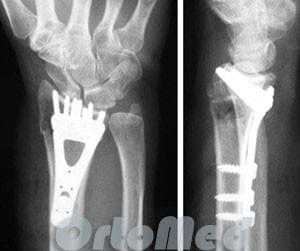

Открытая репозиция перелома лучевой кости

Открытая репозиция накостный остеосинтез пластиной и винтами. Операция включает в себя хирургический разрез, доступ к сломанной кости аккуратно отводя сухожилия, сосуды и нервы, мобилизацию костных отломков, устранение смещения и фиксация в правильном положении. Сломанные кости фиксируются титановыми пластинами, ввиду этого пациенту разрешается ранняя разработка движений в лучезапястном суставе.

До операции:

После операции:

После операции